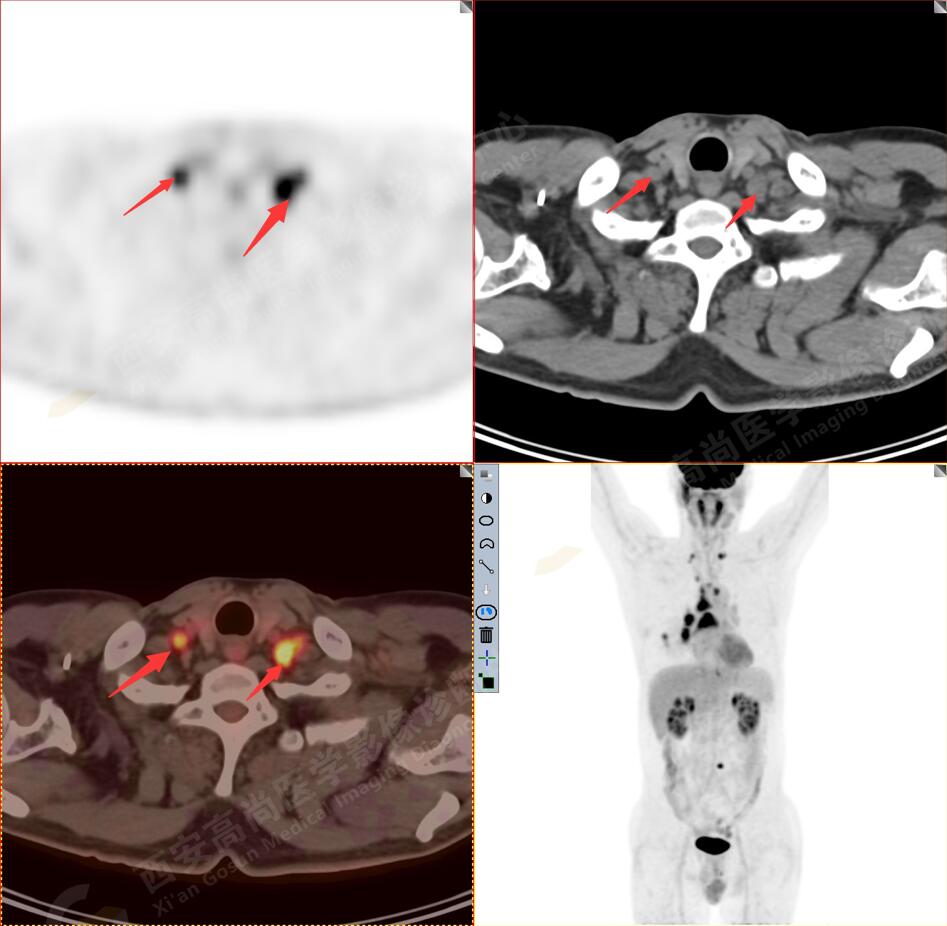

2.以下為全身多發(fā)轉(zhuǎn)移灶

3.右側(cè)肺門、縱隔(1L、1R、3A、4、6、7組)及雙側(cè)鎖骨上多發(fā)腫大淋巴結(jié),呈不同程度FDG代謝異常增高,考慮為淋巴結(jié)轉(zhuǎn)移。